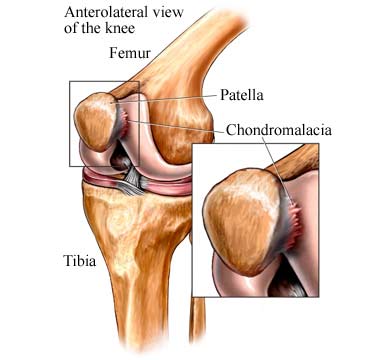

Chondromalacia Explained Causes Symptoms Diagnosis

What Is Chondromalacia Patella Symptoms Causes Diagnosis

Chondromalacia Patella Causes Symptoms Treatment for Knee Pain

Chondromalacia Patella Symptoms Diagnosis Treatment Pantai

What is chondromalacia patella or soft knee patella

Chondromalacia Patella or Patellofemoral Syndrome What s The